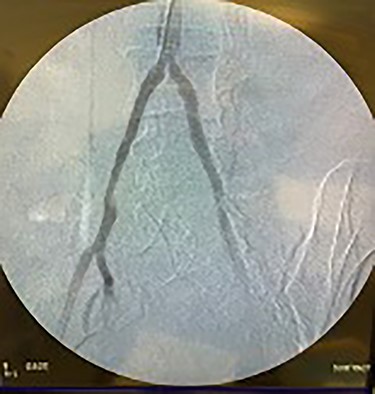

Catheter arteriogram results showed significant occlusion of the left iliac artery (Figs 3 and 4), the right iliac artery (Fig. 1), as well as the distal abdominal aorta (Fig. 2). There were numerous collateral vessels noted, indicating the presence of long-standing proximal stenosis (Fig. 1). The decision was made to use angioplasty to help widen the areas of stenosis. An 8 mm × 40 mm Passeo balloon was advanced from the right femoral artery into the left iliac artery (Fig. 7) and insufflated to 6 mmHg (Fig. 6). The balloon was allowed to remain expanded for 1 min and then was deflated. Next, the distal aorta was repaired in a similar fashion. The balloon was advanced into the distal aorta from the right femoral access and insufflated to 12 mmHg (Fig. 8). The balloon was allowed to remain expanded for 90 s.

Fluoroscopy of right iliac artery showing vast collateral vascular formation, indicating long-standing proximal obstruction.